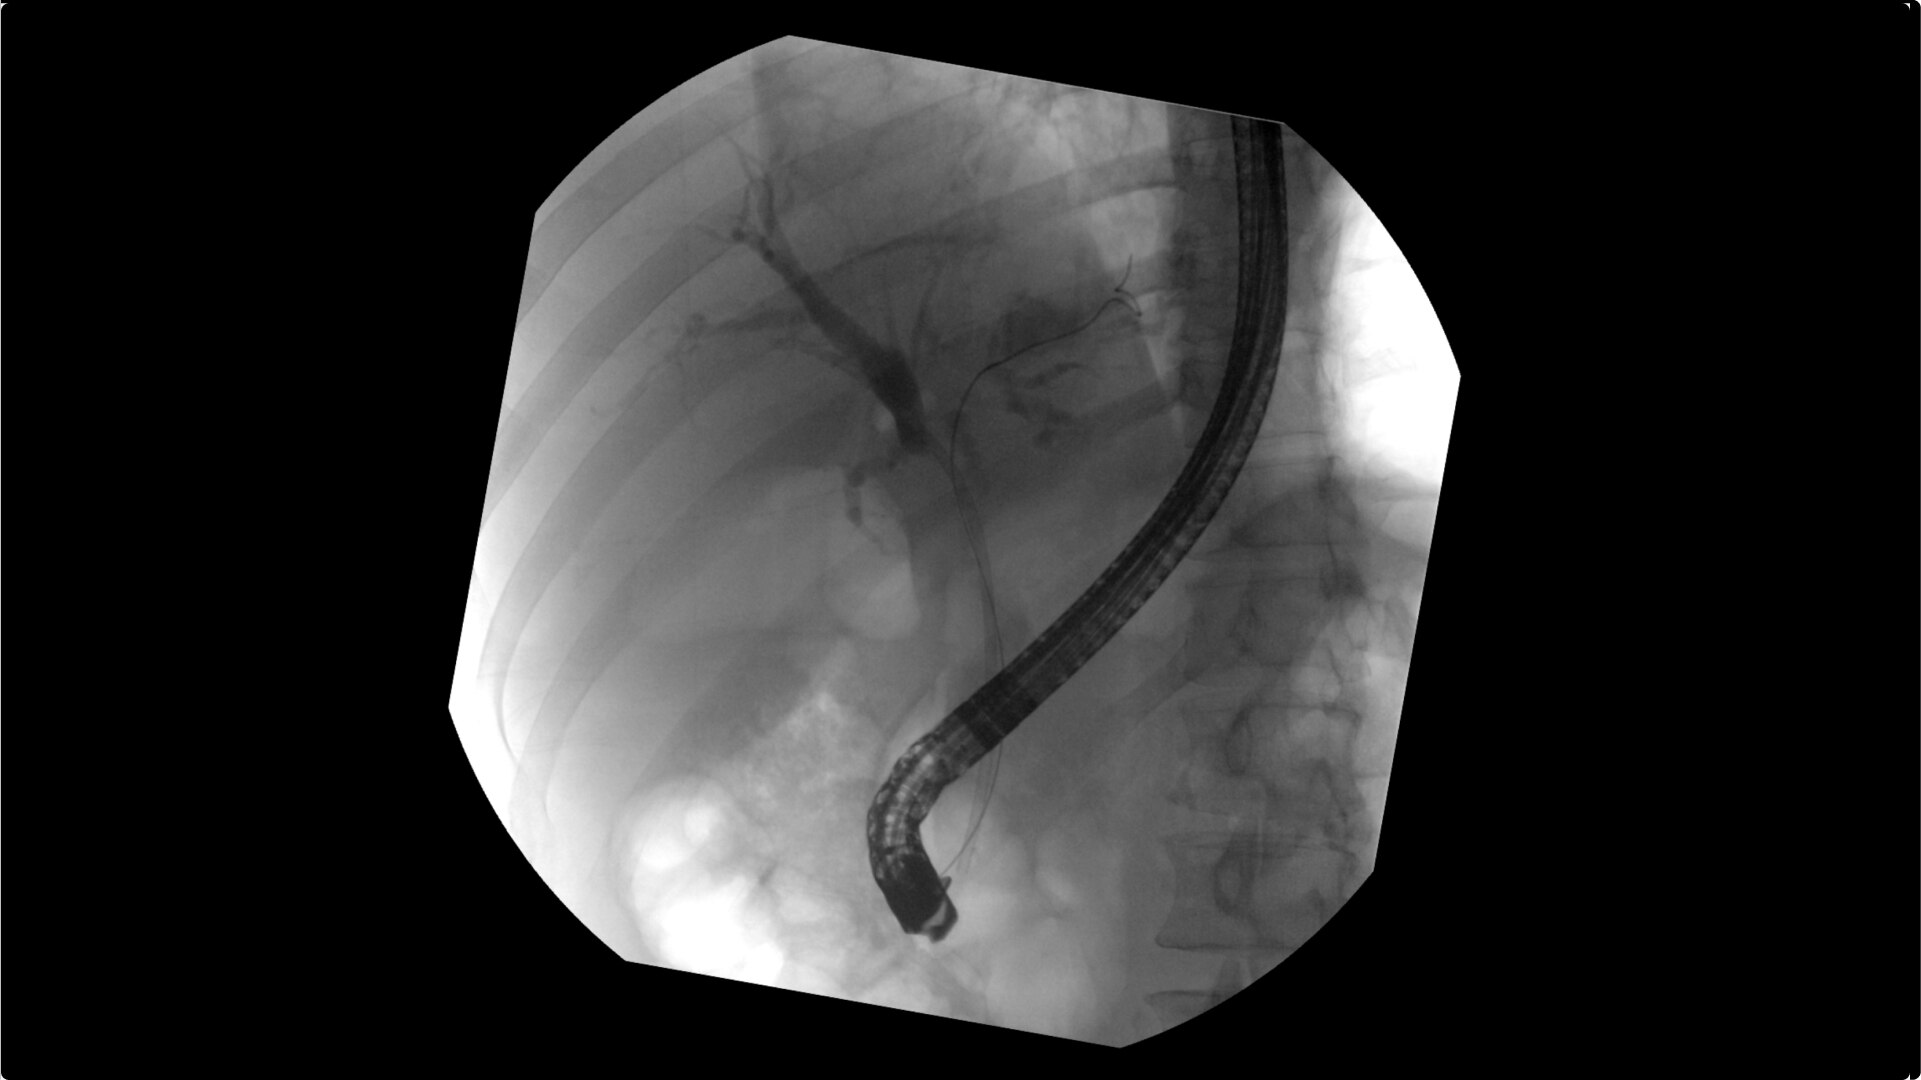

Clearly visualize the GI tract of patients, regardless of size, during a wide range of endoscopic procedures, including ERCP. OEC C-arms offer amazing image quality at low dose and provide enhancements for clear visualization during movement in soft tissue, such as during guidance of low-density drainage tubes or thin biopsy brushes. A large, clear display with comfortable viewing enables effortless workflow.

See detail 1 for 1 from detector to a 4K UHD display for stunning image quality and visualization of low density drainage tubes and thin biopsy brushes.

With OEC Elite CFD, the General HD preset profile optimizes to present high contrast, enhanced edge images to optimally see small detail such as stones in pancreatic duct.

Complex gastrointestinal procedures require powerful imaging systems. OEC premium C-arms perform in a variety of procedures such as:

• Endoscopic retrograde cholangiopancreatography